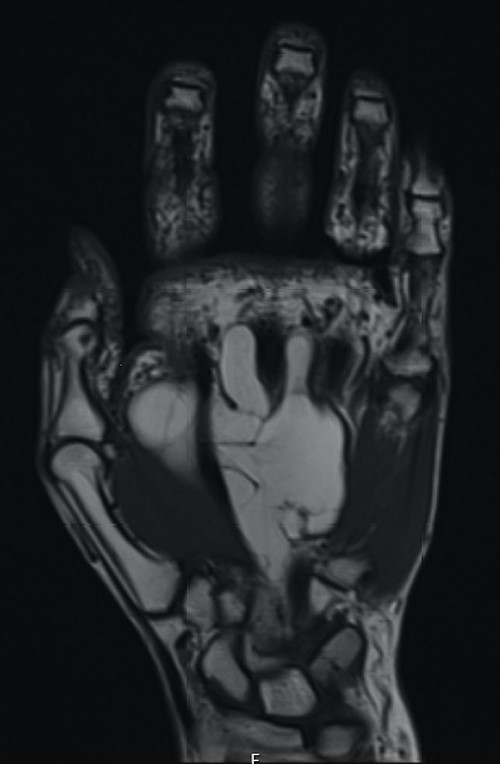

The patient underwent nerve conduction studies, which suggested a carpal tunnel lesion on the left. Magnetic resonance imaging (MRI) of the left hand confirmed the presence of a large, lobulated and well-defined fatty lesion in the palm centred between the flexor tendons and metacarpals, with dorsal and volar extensions (Fig. 1), and a proximal component within the carpal tunnel causing median nerve compression (Fig. 2). The investigations were discussed at the regional sarcoma multidisciplinary team meeting and findings were suggestive of a benign lipoma.

Axial MRI view demonstrating volar and dorsal extension of the fatty lesion from the middle of the palm.